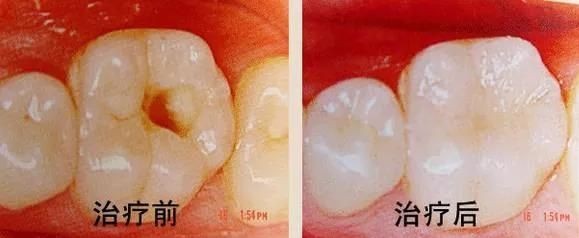

六、龋齿的治疗

对已形成实质性缺损的牙齿,充填术是目前成效较好的方法。